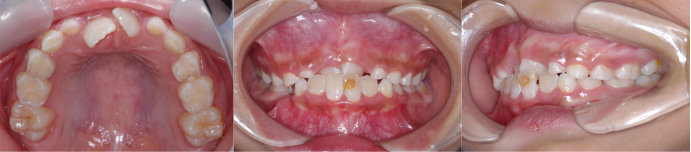

| Case1 |

| 出っ歯 |

| <治療前> |

| <治療後> |

| 主訴 |

前歯が出ている |

| 診断名 |

上顎前突 |

| 年齢 |

8歳 |

| 使用装置 |

マルチブラケット装置 |

| 抜歯部位 |

永久歯の抜歯は無し |

| 治療期間 |

2年4か月 |

| 治療費概算 |

検査・診断料:5万円+税 装置・技術料:25万円+税 おおよそ1か月ごとの処置・管理料:5,000円+税 保定装置料:5万円+税 |

| リスク・副作用 |

う蝕 歯根吸収 |